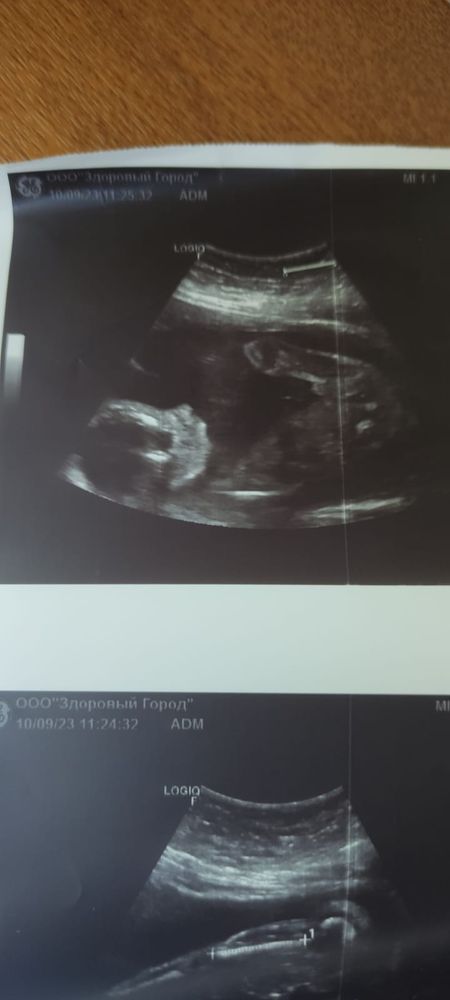

Изображение Паренёк у нас Елизавета,

09.10.2023